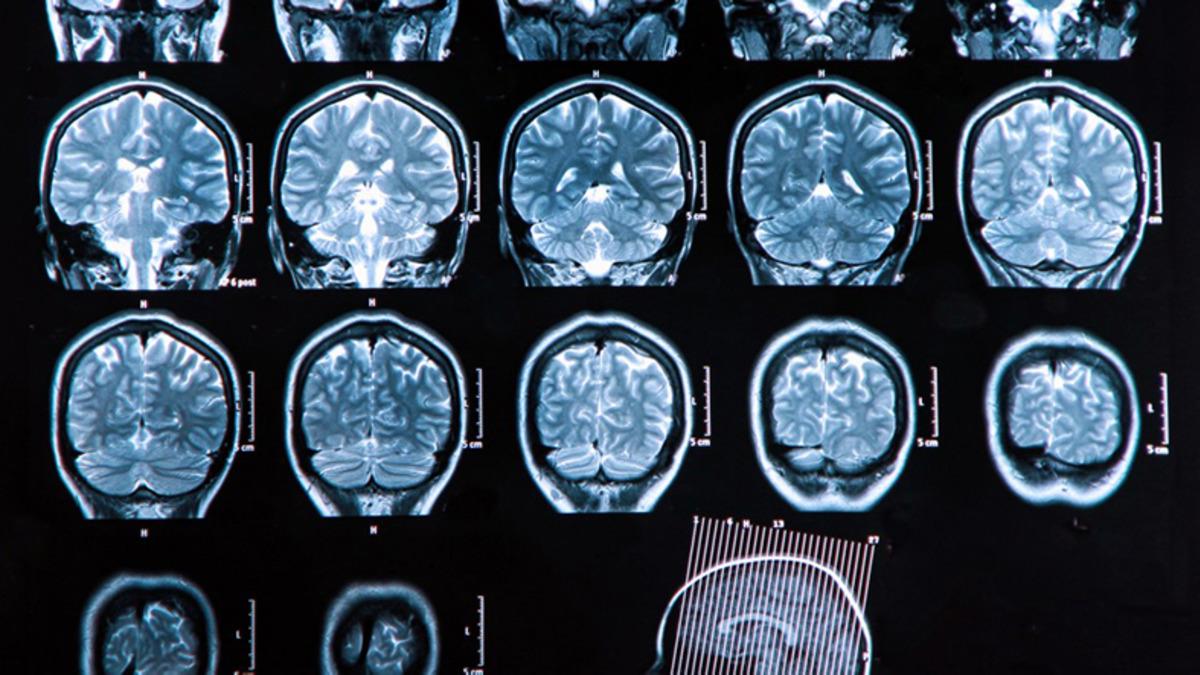

Pennsylvania Üniversitesi’nde yapılan yeni çalışmada üç kıtadan şizofreni hastalarının 300’den fazla MRI beyin taraması HYDRA adı verilen yeni bir makine öğrenme yöntemi ile analiz edildi. Makine öğrenme ile yapılan analiz sonuçları, bazı beyin bölgelerinde düşük miktarda gri madde bulunduğu yönündeki görüşlere meydan okuyor.

Yapılan analizde, şizofreni hastalarının yaklaşık yüzde 40’ının nispeten normal gri madde hacimleri gösterirken, şizofreni hastalarının önemli bir miktarı sağlıklı kontrol grubunun beyin taramalarına kıyasla, striatum adı verilen orta beyin bölgesinde gri maddede küçük de olsa artış gösterdi.